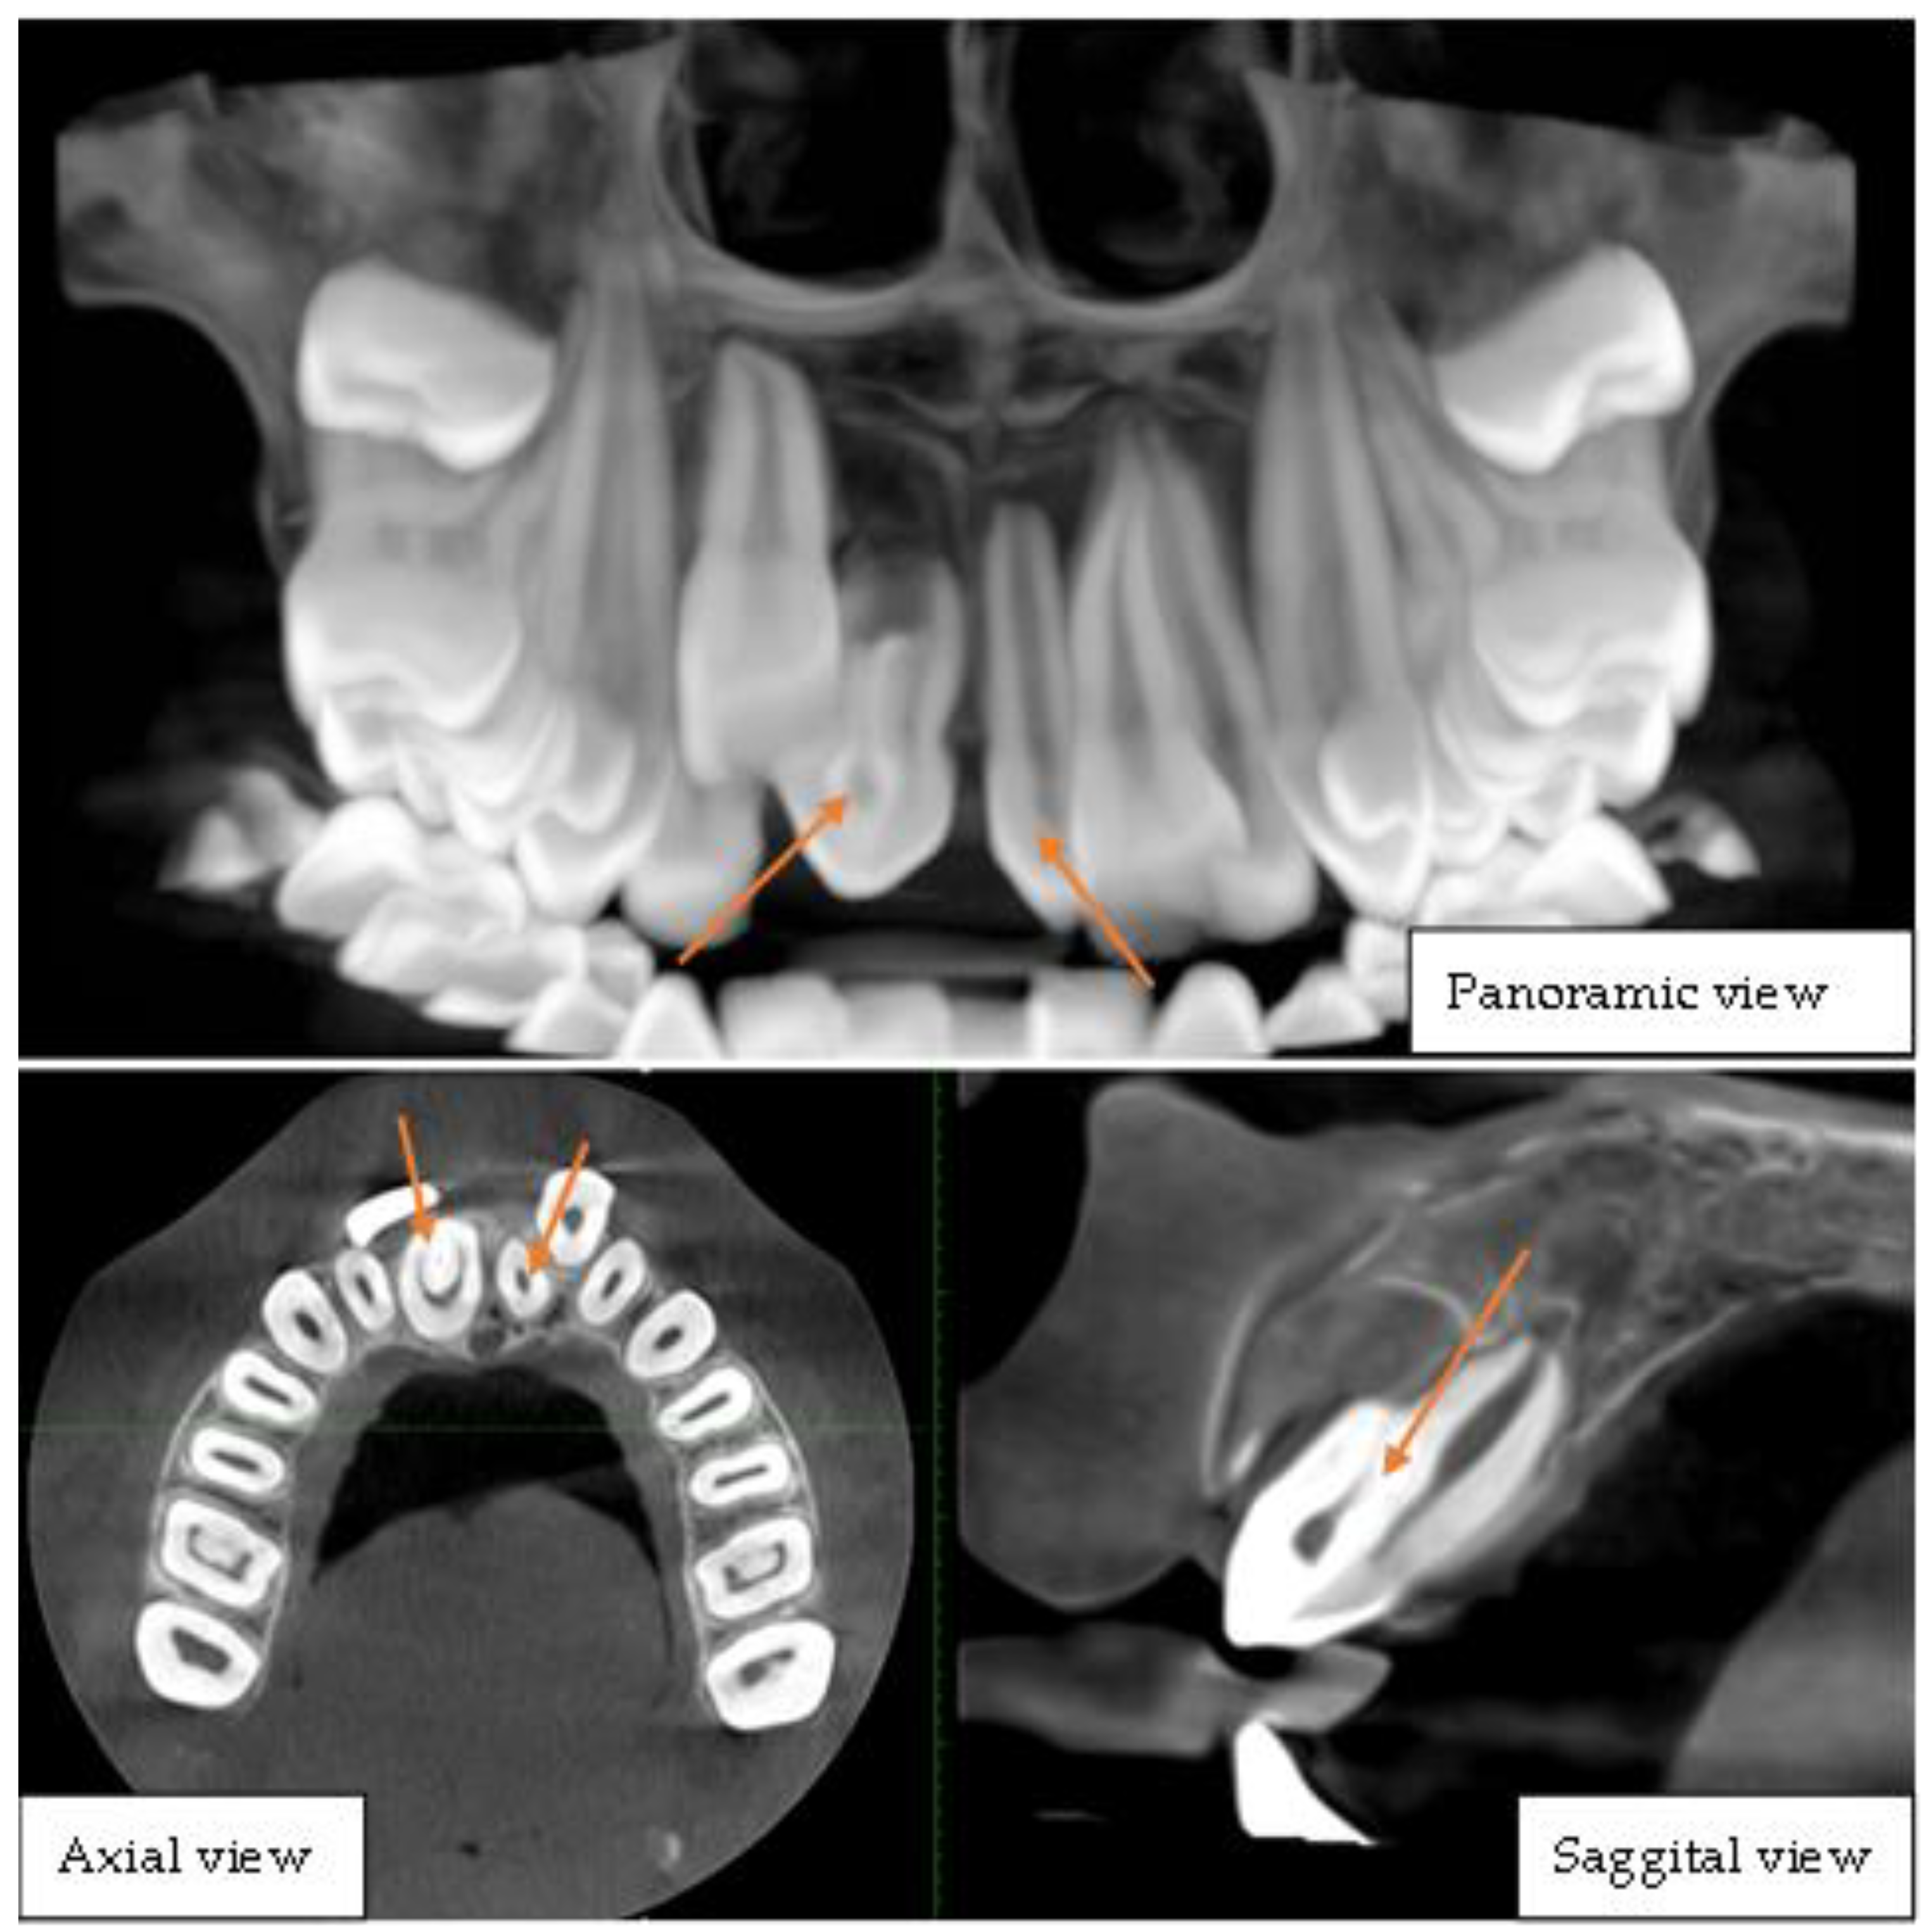

Figure 2. Cone-beam computed tomography of the upper jaw depicting bilateral mesiodens. This CBCT image set comprises panoramic, axial, and sagittal views, providing a comprehensive visualization of dental anomalies in the anterior maxillary region. The panoramic view reveals two mesiodens located in the midline, positioned palatally between the maxillary central incisors, one of which exhibits distinct radiographic features indicative of dens invaginatus, characterized by an infolding of enamel and dentin extending into the pulp chamber, presenting as a radiopaque structure within the tooth. The impacted right central incisor was displaced superiorly and was possibly hindered in its eruption path by the presence of these supernumerary teeth. The axial view clearly shows the mesiodens’ positions relative to the adjacent teeth, confirming their bilateral presence and the invagination pattern within one of them. The sagittal view provides a detailed cross-sectional visualization of the invaginated mesiodens, illustrating the extent of the infolding and its proximity to the pulp chamber. These findings collectively indicate a rare case of bilateral mesiodens with one exhibiting dens invaginatus, which may pose risks of dental complications such as pulp involvement, caries, or periapical pathology. Prompt intervention is crucial to manage the impacted tooth and associated anomalies. Dens invagination is a rare dental anomaly that results from an infolding of the enamel organ into the dental papilla during tooth development characterized by an invagination within the tooth structure [4,5]. Dens invaginatus has a prevalence of 7.45%, with the upper lateral incisor most affected (5.12% unilaterally) and type I as the most common morphology [6,7]. The simultaneous presence of dens invaginatus and mesiodens is exceedingly uncommon, with only a handful of cases reported in the literature [8,9,10]. The rarity of this combination makes its diagnosis and management particularly challenging. This report highlights the rarity of the rare case of dentin invagination in a mesiodens tooth which was later extracted following the treatment plan.